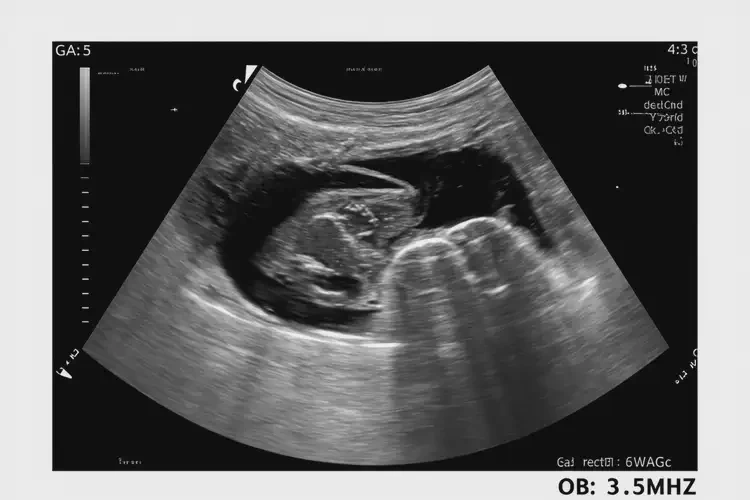

孕5周6天胎心71怎么回事(圖1)

• 超聲波檢查:通過超聲波檢查可以觀察胎兒的心臟結(jié)構(gòu)和功能,評估是否存在心臟問題。